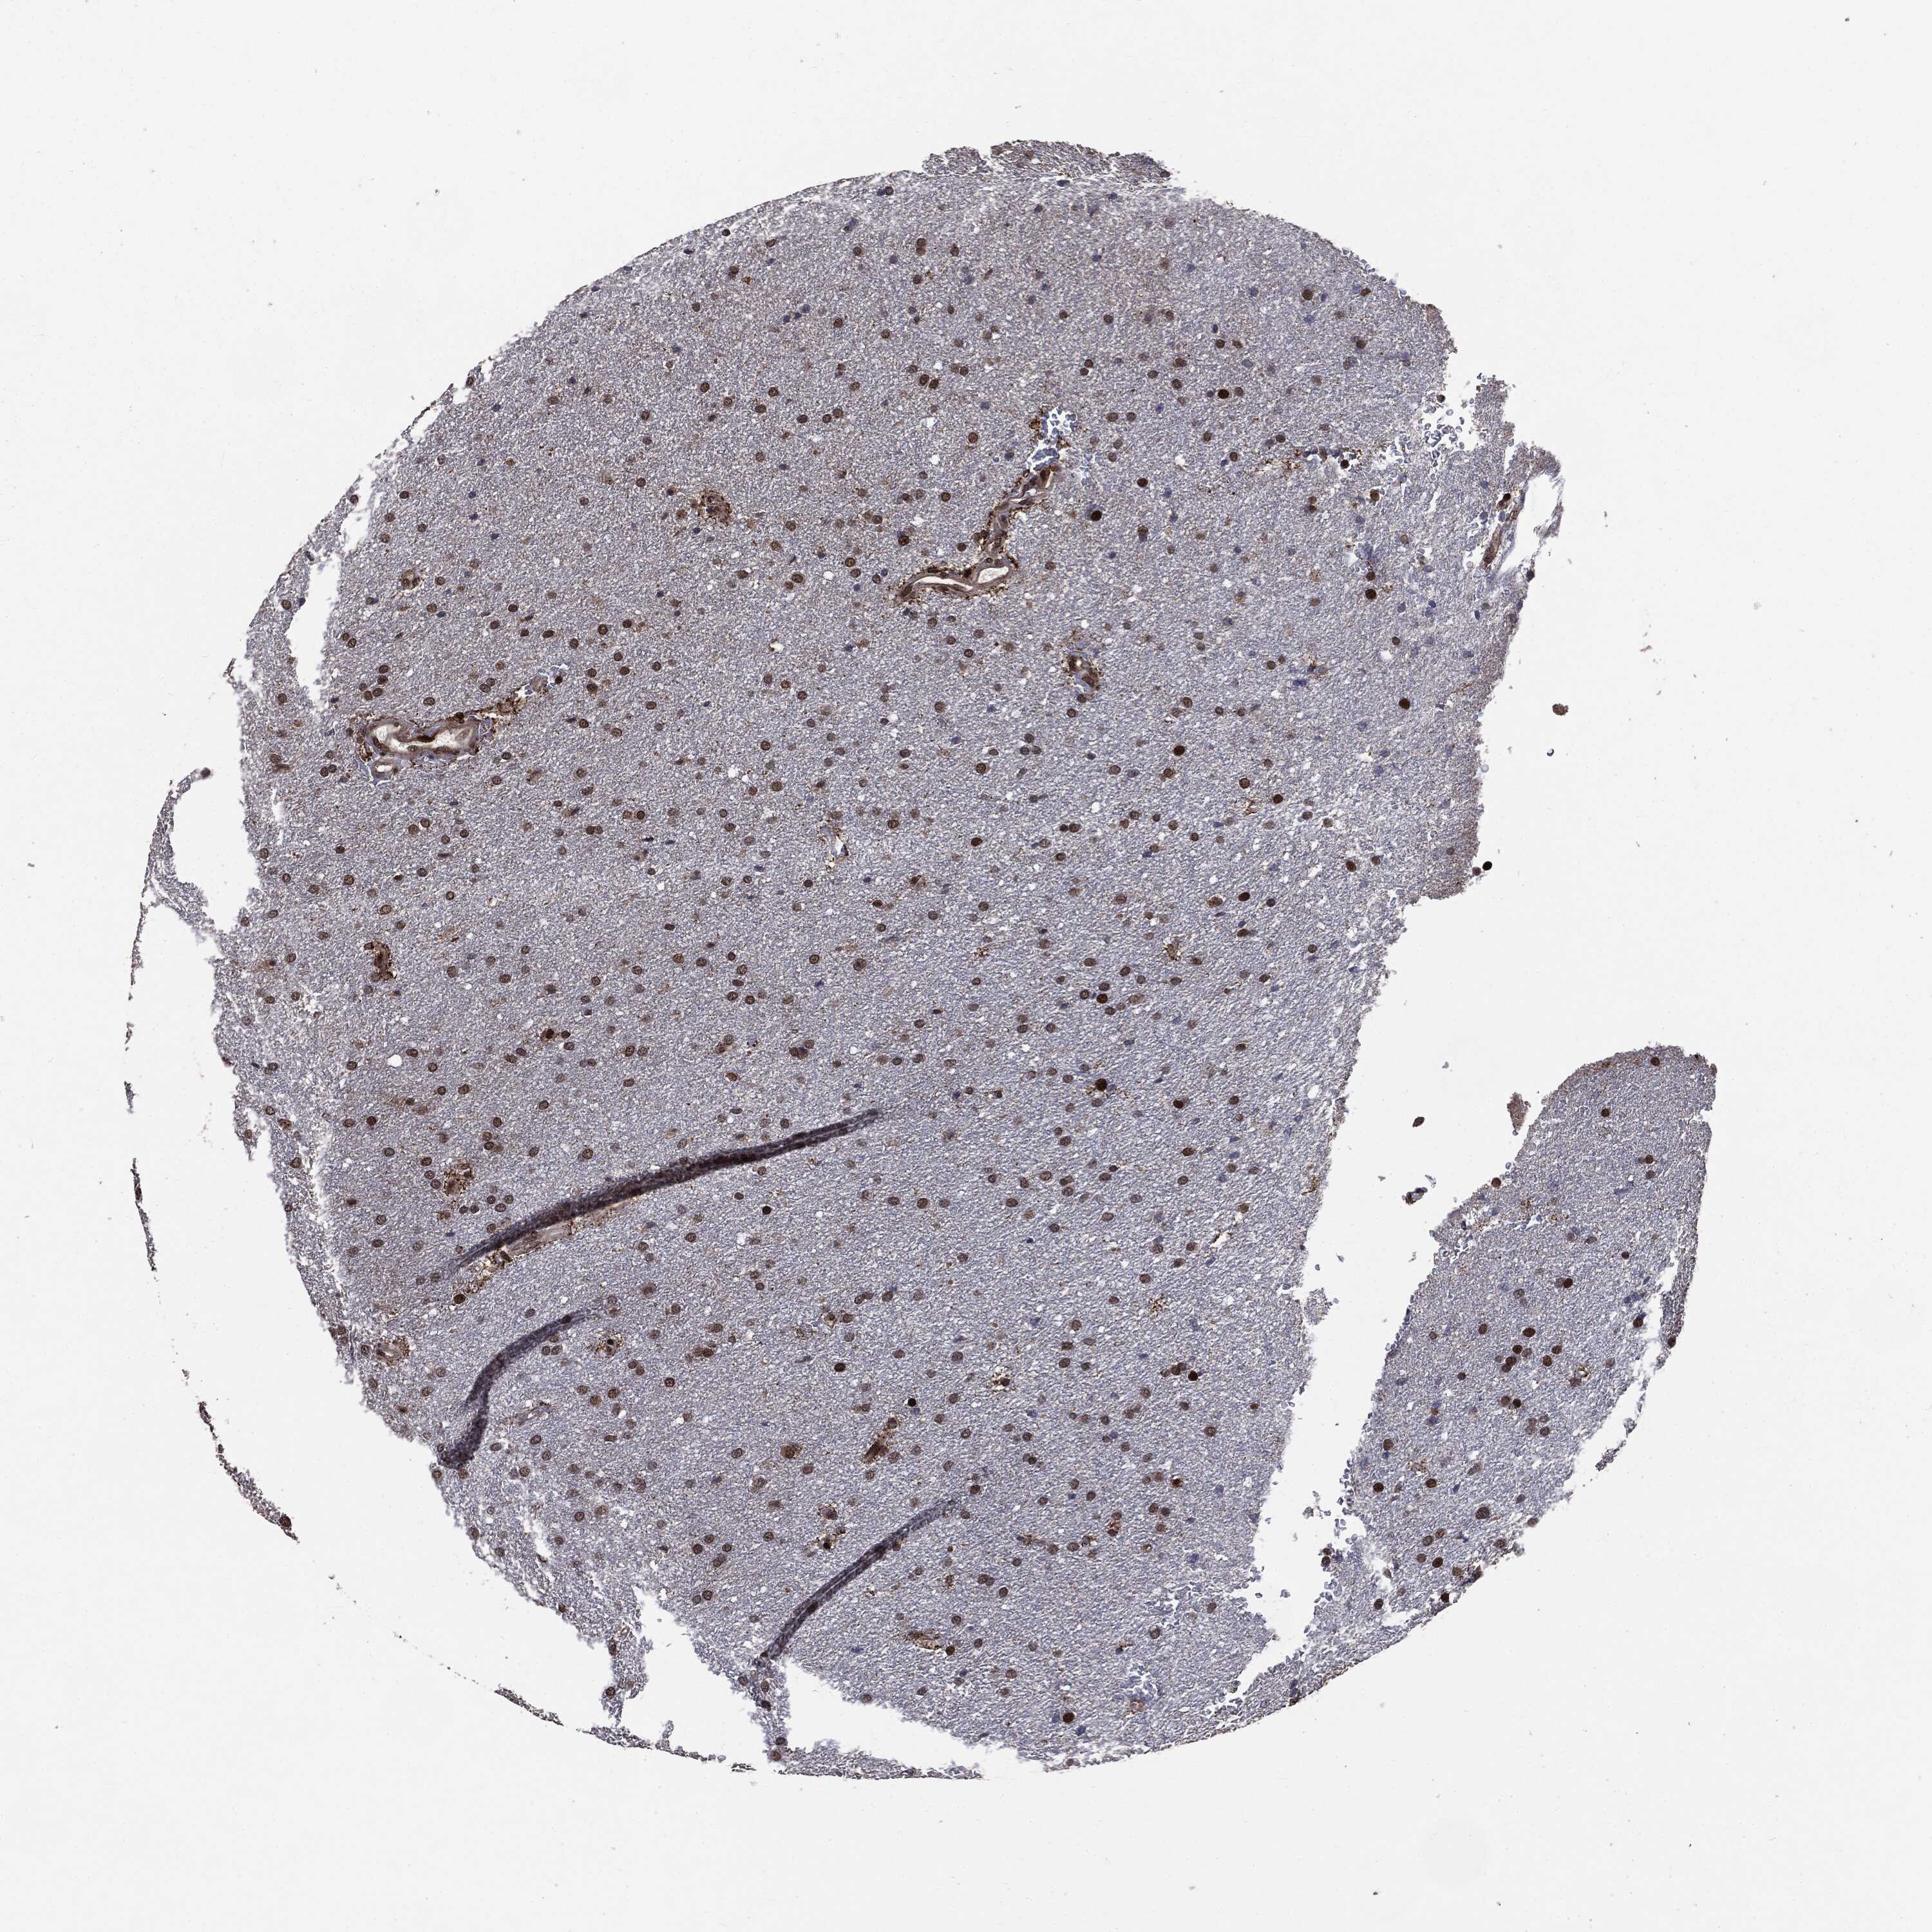

GLIOMA - Protein expressioni

A mouse-over function shows sample information and annotation data. Click on an image to view it in a full screen mode. Samples can be filtered based on level of antibody staining by selecting one or several of the following categories: high, medium, low and not detected. The assay and annotation is described here.

Note that samples used for immunohistochemistry by the Human Protein Atlas do not correspond to samples in the TCGA dataset.

Antibody stainingi

Antibody staining in the annotated cell types in the current human tissue is reported as not detected, low, medium, or high, based on conventional immunohistochemistry profiling in selected tissues. This score is based on the combination of the staining intensity and fraction of stained cells.

Each image is clickable and will lead to virtual microscopy that enables deeper exploration of all samples and also displays staining intensity scores, fraction scores and subcellular localization as well as patient and tissue information for each sample.

Antibody HPA022914

Antibody HPA064732

Staining

High

Medium

Low

Not detected

Intensity

Strong

Moderate

Weak

Negative

Quantity

>75%

75%-25%

<25%

None

Location

Nuclear

Cytoplasmic/membranous

Cytoplasmic/membranous,nuclear

Glioma, malignant, High grade

Glioma, malignant, Low grade

Glioma, malignant, NOS